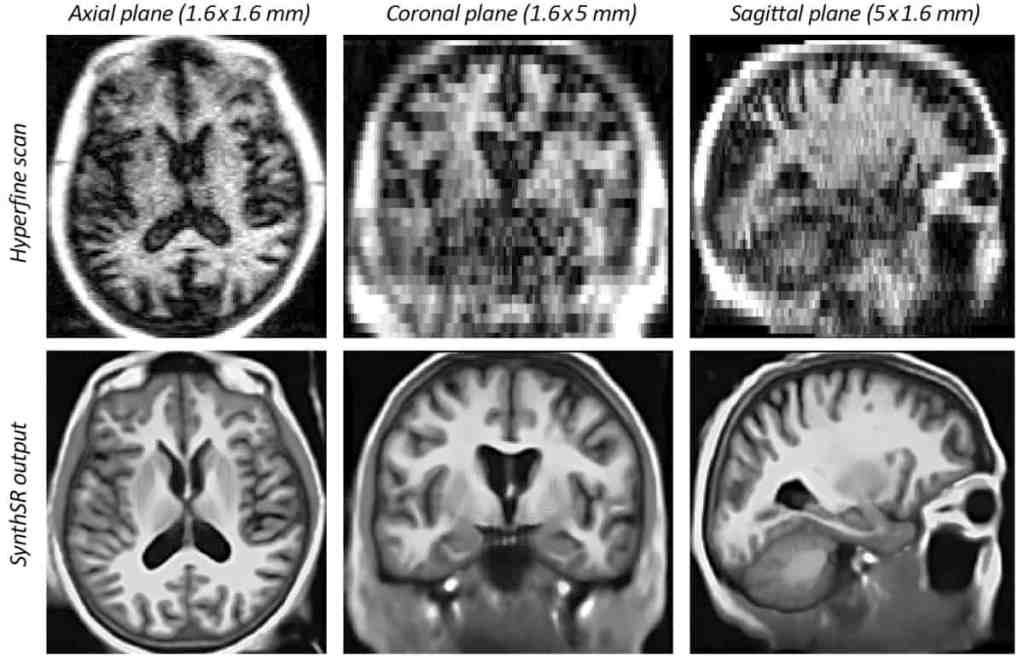

To find a solution, cardiologist Geoff Tison and his team developed an AI model called a deep neural network, which was able to predict the efficiency of the heart’s ventricles. This research could allow medical professionals to accurately diagnose patients, while limiting the use of harmful substances. Further studies have shown AI’s capacity to recognize illnesses early on by presenting images of both healthy and unhealthy organs to AI and training it to spot the anomalies. Codeveloper of this new AI algorithm John Mongan, MD, PhD explains: “I think of this as an additional safety check that can deliver diagnoses and patient care sooner.” Within the sector of pathology, AI has also been used to identify tissue anomalies on a cellular level by enhancing slide processing and making disease detection more accurate. Similarly, AI’s ability to inspect images could aid physicians in recognizing various cancers before they reach a critical stage. Although artificial intelligence is an extremely powerful tool in healthcare, it remains an algorithm capable of making mistakes, confirming the importance of radiologist verification.

Credit: Physics World –